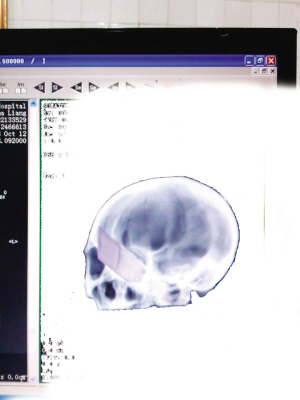

影像:脑部差点刺穿

为精确还原刀刃在脑内的情况,必须要有影像。“但这个伤做影像很难。”杨夏医生解释道,由于是金属物质,不能做核磁共振,也不能做影像检查,金属会造成投影中出现伪影,照出来的影像照片经常是黑巴巴一片,掩盖了刀刃周围的正常组织,也无法判断刀刃在脑中的真实情况。

影像科的工作人员启动了最先进的特殊处理技术,经一个多小时的后期处理,还原了脑内情况:插入伤者唐某的刀刃已有12.5公分,全刀长约30公分,刀刃有16.5公分,“也就是说,刀刃几乎全部由眼眶插入了脑部。”影像医生说,从图像中能看到,刀刃刚巧划过伤者颅底,触及左侧颈椎椎体,差点把整个脑袋刺穿。